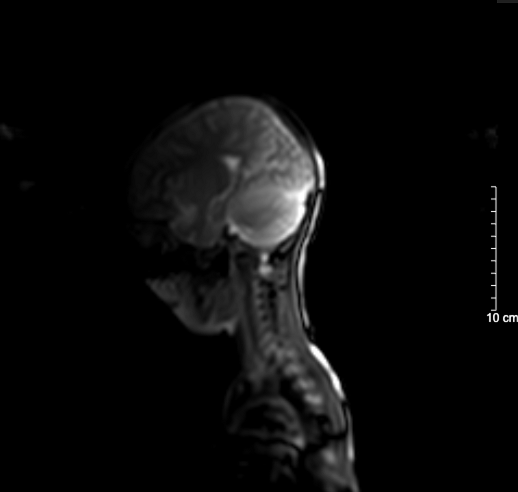

Kết quả chụp não, cột sống cổ bệnh nhi sau 5 ngày nhập viện bình thường

BSCKII. Doãn Phúc Hải – Trung tâm Nhi khoa, Bệnh viện Bạch Mai trực tiếp điều trị cho bệnh nhi chia sẻ: Thân nhiệt của bệnh nhi được hạ nhanh xuống và kiểm soát duy trì ở mức 34°C, giảm tổn thương, tái tưới máu tại não, tăng tỉ lệ sống và hồi phục chức năng thần kinh. Sau 72 giờ điều trị hạ thân nhiệt chủ động, bệnh nhi được nâng thân nhiệt, làm ấm trở lại về mức bình thường và duy trì theo dõi trong 48 giờ. Khi thân nhiệt trở lại bình thường, bệnh nhi tỉnh dần và được rút ống thở. Dấu hiệu sinh tồn ổn định, tri giác nhận thức tốt. Sau 5 ngày nằm viện, bệnh nhi đã tỉnh táo hoàn toàn. Kết quả chụp tim, phổi, MRI sọ não, cột sống cổ không thấy bất thường. Đây cũng là trường hợp đầu tiên trẻ 5 tuổi tự “thắt cổ” mà chúng tôi bắt gặp.